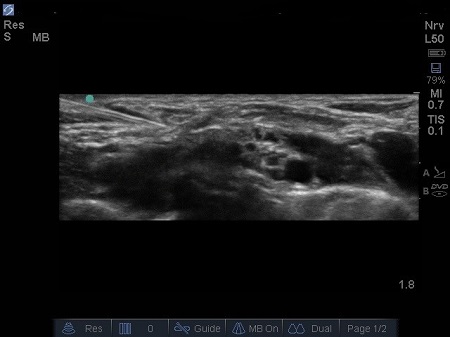

- A mirror or reverberation artefact of the Subclavian Artery often occurs, mimicking a second Subclavian Artery beneath the rib. See Fig.

Fig.4. Mirror artefact of subclavian artery